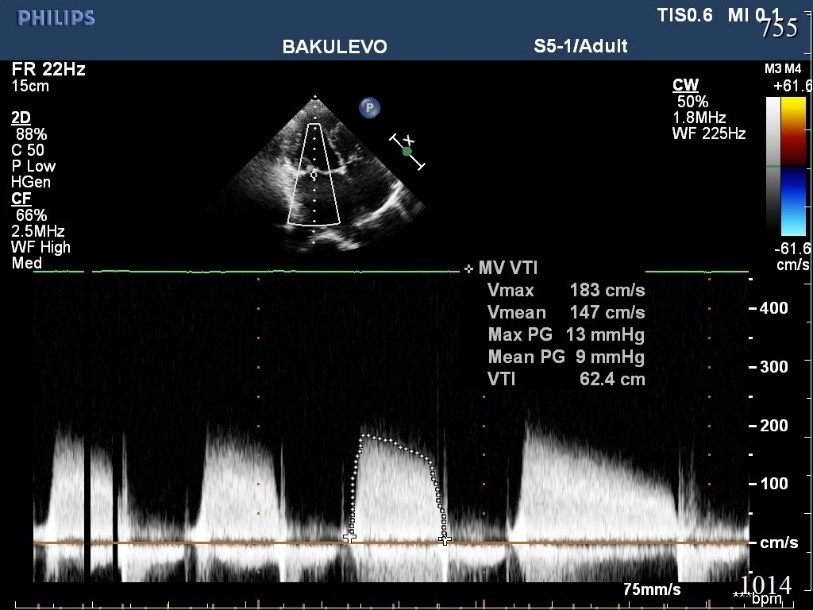

1917. Патологическим состоянием, показанным на эхокардиографическом изображении, является